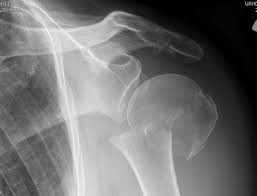

Question 2:

A 28-year-old male sustains a severe hyper-dorsiflexion injury to his ankle in a motor vehicle accident, resulting in a Hawkins Type III talar neck fracture. Which of the following arteries provides the predominant blood supply to the body of the talus, placing it at significant risk for avascular necrosis in this injury?

Correct Answer: Artery of the tarsal canal

Explanation:

The artery of the tarsal canal, which is a branch of the posterior tibial artery, provides the dominant blood supply to the talar body. In a Hawkins Type III fracture (talar neck fracture with subtalar and tibiotalar dislocation), the blood supply from the artery of the tarsal canal, the artery of the sinus tarsi, and capsular vessels are disrupted, leading to an avascular necrosis (AVN) rate approaching 100%.